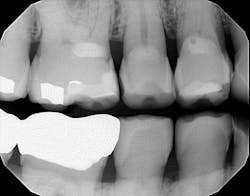

Radiographically, the first thing I noticed were the tabletopped occlusal surfaces (figures 1 and 2). Clinically, the same was evident, along with generalized wear facets on the posterior teeth (figures 3 and 4). The bite was deep (figures 5 and 6), and the lower anterior teeth had been worn down to half their original size. There were new ceramic crowns on nos. 21, 28, and 29. I also noted that there was an occlusal stop/resin on no. 13, but there was no significant effect on his occlusion as it was even on the right and left sides.